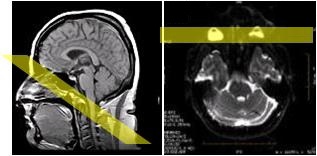

DWI and DTI ring artifact

A ring-like artifact from intense orbit signal can occur on T2-weighted EPI DWI/DTI, ADC/eADC, and Synthetic DWI images.

Position an angled anterior SAT band over the orbits (not the cortex) to suppress the orbit signal intensity and thus minimize the artifact.